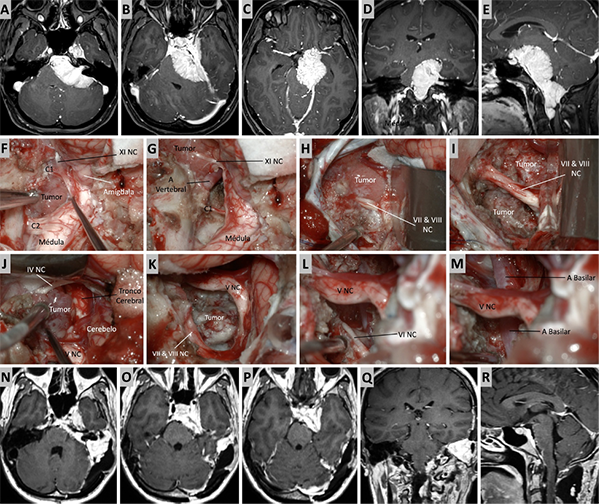

Figura 7. Caso ilustrativo #5. Resonancia que muestra MRPC con implantación petroclival y extensión a la fosa media. Paciente con audición conservada. A-D. Se presentan las imágenes prequirúrgicas, corte axial, coronal y sagital. E. Se realizo un abordaje presigmoideo combinado con un abordaje subtemporal. Se logro una visión directa del tumor, desde la región del clivus medio hasta la fosa media. F. Se observa una resección tumoral del clivus medio y fosa media casi total. G. Lesion tumoral en clivus medio. H-J. Resección casi total del tumor. La retracción del lóbulo temporal fue necesaria para tener mayor visibilidad de la incisura tentorial. K-N. RMN posquirúrgica donde se observa una resección quirúrgica casi total.

Figura 8. Caso ilustrativo #6. Resonancia que muestra MRPC con implantación petroclival y extensión a la fosa media. A-D. Se presentan las imágenes prequirúrgicas, corte axial, coronal y sagital. E-J. Se realizo un abordaje presigmoideo combinado con un abordaje subtemporal, logrando una exposición del seno sigmoideo y una visión directa del tumor consiguiendo una resección total. K-M. RMN posquirúrgica donde se observa una resección quirúrgica total.

Figura 9. Caso ilustrativo #7. A-B. Meningioma de la MRPC con implantación petrosa anterior. C-F. Se realiza un abordaje subtemporal y petrosectomia anterior. G-H. Imagen por RMN. Resección completa.

Figura 10. Caso ilustrativo #8. MRPC con implantación petroclival con invasión con extensión a la fosa media, clivus inferior, agujero magno y región premedula. Paciente con anacusia izquierda. A. Se observa un corte axial. MPC con extensión al ángulo pontocerebeloso y compromiso del CAI. B. Se observa extensión del tumor a la fosa media, seno cavernoso y ala mayor del esfenoides. C. Se observa extensión del tumor a ala menor del esfenoide, cisterna silviana y optocarotidea.D-E. Extensión del tumor a la fosa media, al clivus inferior y a la región premedular. Se realizo un abordaje presigmoideo acompañado de un abordaje far-lateral y un abordaje retrosigmoideo. F. Se observa la porción tumoral ubicada en el foramen magno y la región premedular, fue necesario un abordaje far-lateral. G. Resección completa de la porción ubicada en foramen magno y región premedular. H. Porción tumoral que se extiende desde clivus inferior a clivus medio. I-J. Resección de tumor de clivus medio e inferior. K. Porción tumoral en clivus superior con extensión a fosa media. Se realizo un abordaje transpetroso anterior para esta región. L-M. Resección casi total. N-R. Imágenes postquirúrgica que muestran una resección casi total.